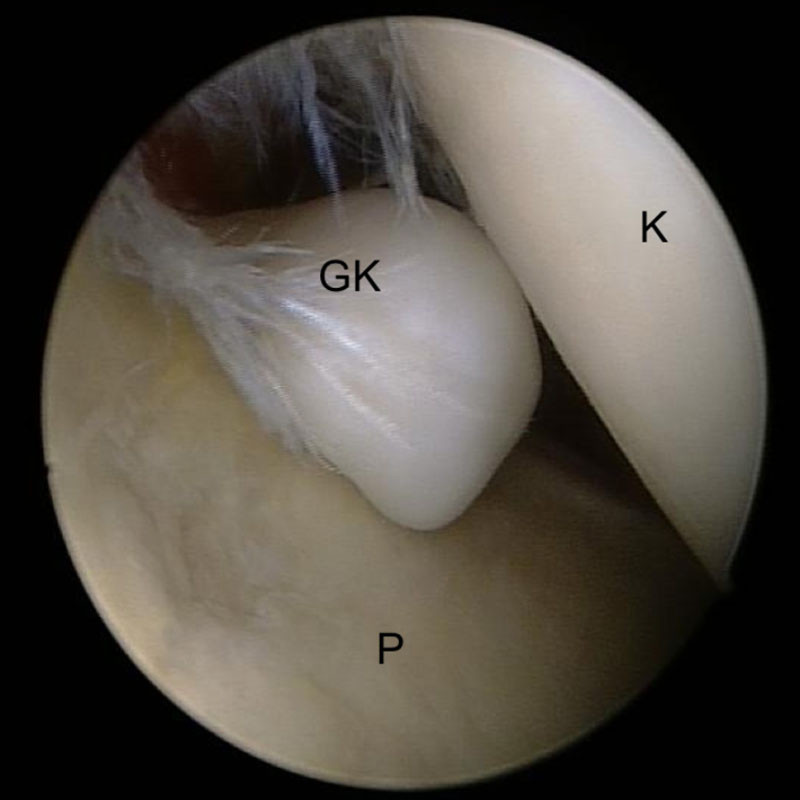

Ein freier Gelenkkörper zwischen Oberarmkopf und Pfanne

Ein freier Gelenkkörper (GK) zwischen Oberarmkopf (K) und Pfanne (P) bei der Arthroskopie